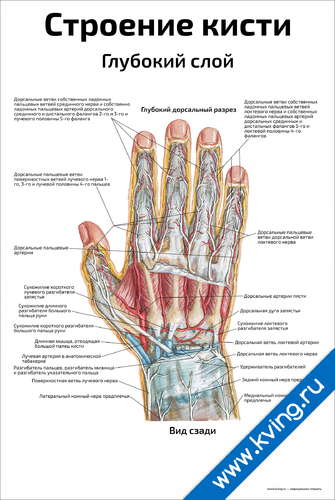

Анатомия кисти руки и строение костей